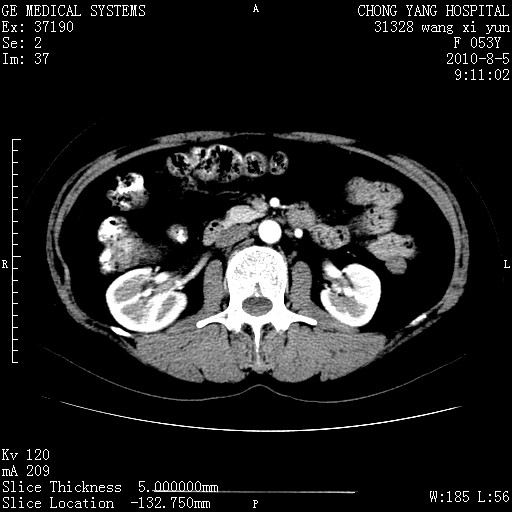

标题: CT28214:F41Y 血尿二十天,建议盆腔平扫加增强。

1)考虑肝左叶胆管细胞癌。2)脂肪肝。